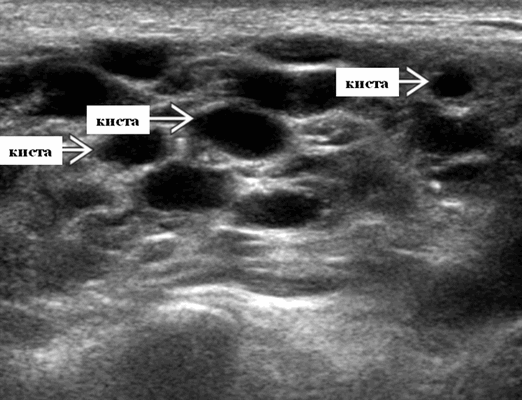

4. УЗИ при лимфоэпителиальном поражении околоушной железы при ВИЧ:

• Находки могут варьировать от простых кист до смешанных новообразований с преобладанием солидного компонента:

о Кисты не являются полностью анэхогенными, внутри них могут находиться кровоснабжаемые перегородки

о Солидные образования могут напоминать опухоль околоушной железы

- Серошкальное УЗИ. Спектр сонографических находок от простых кист до смешанных и солидных образований. Кистозные, смешанные и солидные поражения могут возникать одновременно в околоушных железах. Кистозные поражения (кисты ДЛК). Хорошо очерченная киста, разного размера, от анэхогенной до гипоэхогенной структуры с задним акустическим усилением. Сеть тонких перегородок ± муральные узлы. Часто встречаются внутренние эхо, которые могут быть мобильными. Сотовидная внешность паренхимы околоушной железы, когда она диффузно изменена з а счет кист. Смешанные поражения (ДЛП). Границы могут быть плохо очерченными, разного размера. Структура преимущественно гипоэхогенная, железы могут быть неоднородными. Без заднего акустического усиления. Солидные поражения (околоушная лимфаденопатия). Множественные овальные / круглые, гипоэхогенные, внутрипаротидные лимфоузлы на УЗИ. Четкий корковый слой ± сохранная корневая архитектура. Сопутствующая реактивная шейная лимфаденопатия